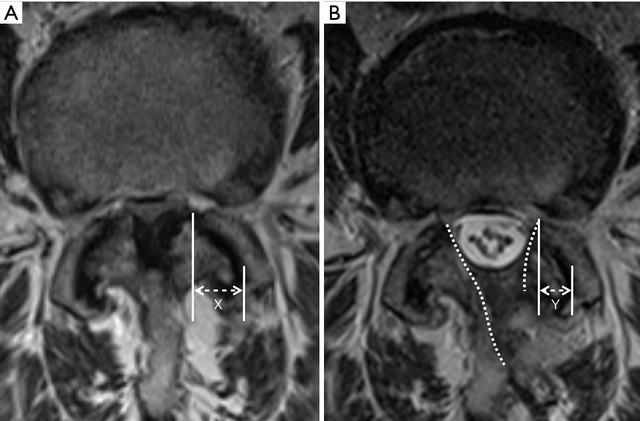

2.3 成果评估术前和最终的X射线检查,包括静态和动态影像进行了评估,以评估节段性不稳定。术前和术后3个月进行了腰椎的MRI检查,测量了最狭窄的轴向硬脊膜横截面积(CSDA),以评估减压效果,每次测量重复3次以获得平均值。MRI轴位进行小关节保留情况的评估(图5)。

图5 术前(A)和最终随访(B)MRI上小关节关节保存的测量。虚线突出了减压术的范围。小关节保留的百分比= Y / X×100%。

UBE减压后,狭窄的椎管明显扩大,在MRI上最狭窄的轴向图像上测得的硬脊膜横截面积CSDA从71.4±36.5 显着增加到177.3±59.2 平方mm(P <0.005,配对t检验)。CSDA平均增加105.9±39.5平方mm,比术前增加201.9%±188.0%。切口侧小关节保存的百分比为84.2%±9.3%,对侧为92.9%±6.2%(P = 0.024,配对t检验)(图6)。

在脊柱的后柱稳定结构中,小关节复合体是最重要的。生物力学测试表明,超过50%的小关节破坏会导致脊柱节段不稳定,所有的微创手术方法旨在获得充分椎管减压的同时尽量保留小关节复杂的完整性。UBE通过内窥镜检查方法,可以将外科医生的视点推进到椎板内部或对侧侧隐窝,因此可以最大程度保留小关节。如果使用30度内窥镜,视野将更广泛。本研究中发现,UBE椎管减压足够充分的同时,小关节也得到了很好的保留,切口入路侧小关节保留率为84.2%,对侧为92.9%。